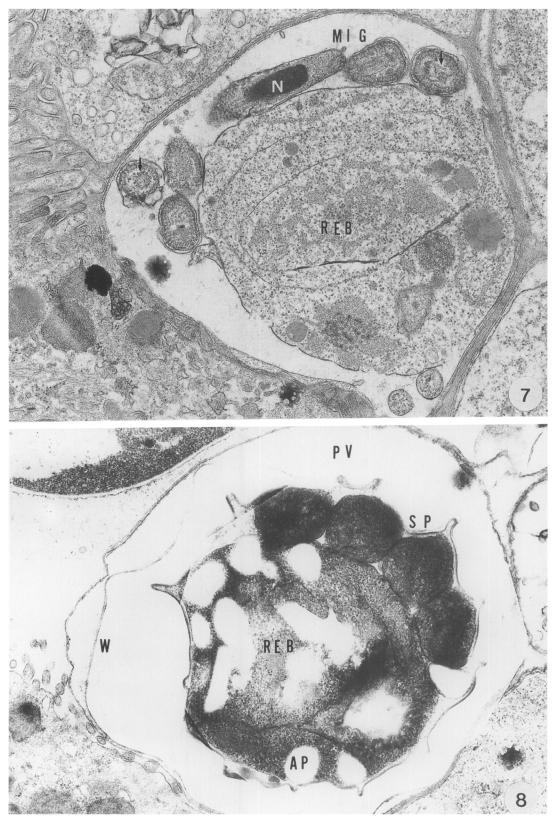

Fig. 2

Most abomasal peptic glands (arrow) of an infected kid are filled with large numbers of various Cryptosporidial forms, × 350, HE.

Structure of developmental stages

On light microscopy, Cryptosporidia were seen in the abomasal peptic glands of an infected kid. Most glands were found infected, and various developmental stages were observed from the apex to the orifice of the glands (Fig. 2). Under transmission electron microscopy, all developmental stages in the parasitophorous vacuoles (PV) were found in the pits of the gastric glands. The endogenous development of the parasite occurred in the microvilli of the surface mucus cells of the gastric glands. A projection of the parasite, which was called a "knob like projection" by Tyzzer (1910), was seen at the attachment site to the host cells. The outer aspect of the projection was surrounded by a thick, filamentous process of the host cell.

Fig. 2 Most abomasal peptic glands (arrow) of an infected kid are filled with large numbers of various Cryptosporidial forms, × 350, HE.